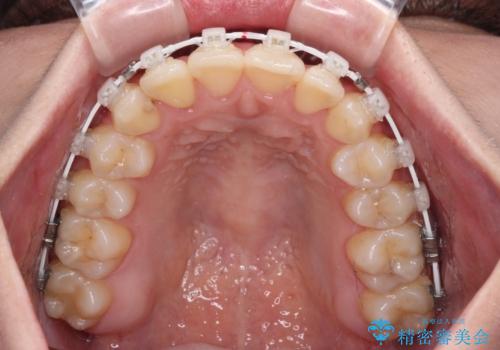

前歯のクロスバイトを短期間で解消 目立たないワイヤー矯正

- 審美装置

- 1年1ヶ月

- 前歯のクロスバイトを治したいとのことで来院された患者様です。

できる限り楽して、短期間で治したいとのことで、ワイヤー装置にて矯正治療を行うこととしました。